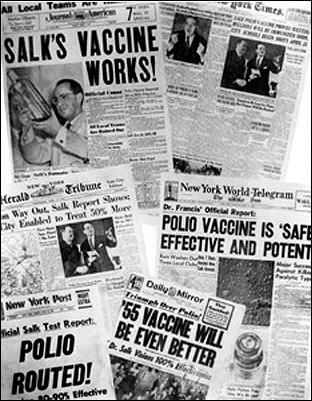

1955年4月12日

这一天见证了Jonas Salk发明的脊髓灰质炎灭活疫苗的巨大成功。180万的儿童参与了这个灭活疫苗的试验,这个疫苗最终被证实是安全、有效且强大的。